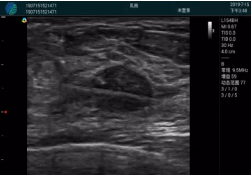

清晰顯示腺體內(nèi)低回聲快影,邊界清晰,包膜較光滑

腺體內(nèi)部清晰顯示一低回聲塊影,形態(tài)不規(guī)則,邊界模糊,邊緣呈毛刺狀,內(nèi)部見砂礫樣鈣化